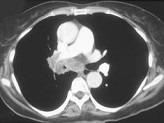

- 单项选择题男,56岁, 咳嗽,咯血1月余, 有吸烟史30余年,结合CT检查图, 选出最可能的诊断 ( )

E、中央型肺癌